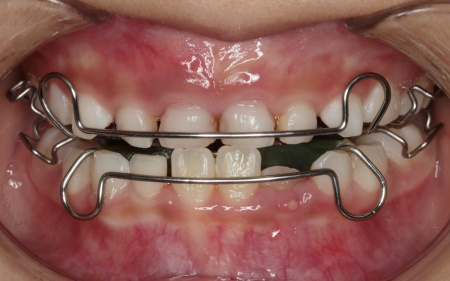

今回の治療では、床(しょう)矯正装置のひとつである「拡大床」という装置を使用した治療法をおすすめしました。

床矯正装置とは、プラスチックの土台部分がある取り外し式の矯正装置の総称です。拡大床は、そのなかでも顎の幅を拡大することを目的とした装置で、中央に組み込まれたスクリューと呼ばれるネジを少しずつ回すことで、顎の横幅を徐々に広げていきます。

まずは患者様専用の拡大床を製作し、装着を開始します。

治療中は、スクリューを少しずつ回すことで顎の骨が徐々に横方向に拡大されていき、永久歯が生えるためのスペースを十分に確保することができました。

治療中